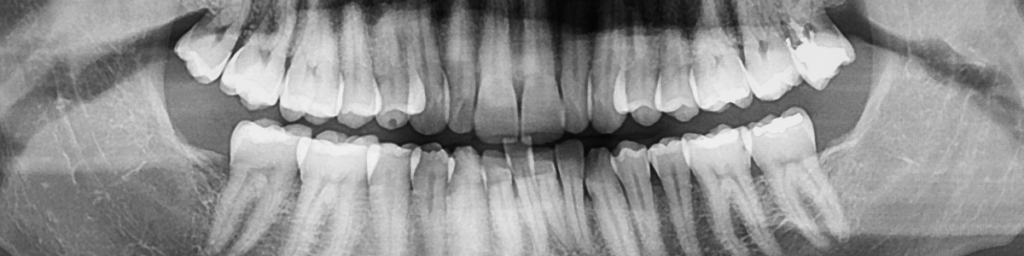

歯科用CT(3DX)による「骨の立体評価」

歯周病の深刻度は、歯を支える「骨(歯槽骨)」がどれだけ、どのように失われているかで決まります。

当院の歯科用CTは、従来の平面的なレントゲンでは決して分からなかった骨の吸収状態を、三次元の立体画像として「可視化」します。

骨の吸収形態の特定

骨が水平的に平らに溶けているのか。あるいは、特定の歯の周りだけが垂直的に深くえぐれるように溶けているのか(垂直性骨欠損)。

この「溶け方」の診断こそが、後述する「再生療法」が可能かどうかを判断する上で、もっとも重要な情報となります。

病巣の広がりと根の状態の把握

CTは、歯の根の周囲に膿の袋(根尖病変)が合併していないか、あるいは歯の根に微細な亀裂(破折)が入っていないかといった、歯周病を悪化させる他の要因をも正確に診断します。